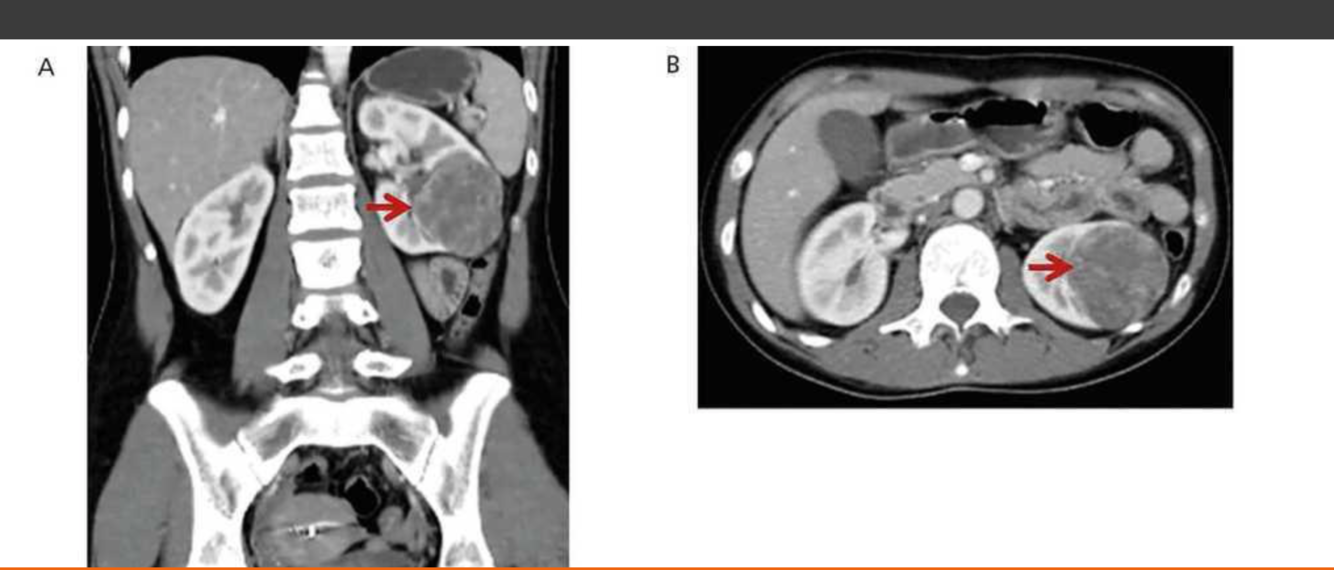

Juxtaglomerular Tumor (Reninoma)

Reninoma is a tumour of the cells of the juxtaglomerular apparatus that produces excessive amounts of renin, resulting in a secondary form of hyperaldosteronism, manifesting clinically with hypertension (HT) and hypokalaemia1. This renal tumour is predominant in females, with a peak incidence between the second and third decade of life and, although uncommon, it is a treatable cause of HT2. It should be suspected in any patient with refractory HT associated with hypokalaemia and high levels of aldosterone.

We present the first case of reninoma reported in Argentina in a young woman with refractory HT and hypokalaemia.

In 1967, Robertson et al.6 reported the first renin-producing tumour. Kihara et al. later called them “juxtaglomerular cell tumours”7. These tumours are very uncommon, with their incidence peaking between the second and third decade of life and they are predominantly found in females, originating in the myoendocrine cells of the renal juxtaglomerular apparatus, although the production of renin by different tumours has also been demonstrated, such as Wilms tumours, carcinoid tumours, renal oncocytoma and renal cell carcinoma8,9. In accordance with the presence or absence of symptoms, JCT may occur as: a “typical” variant in the majority of cases and manifests with HT, hypokalaemia, high plasma renin and secondary hyperaldosteronism; an “atypical” variant, in which HT is not accompanied by hypokalaemia; and a third “non-functioning” variant, which occurs without HT and with normal levels of potassium10,11.